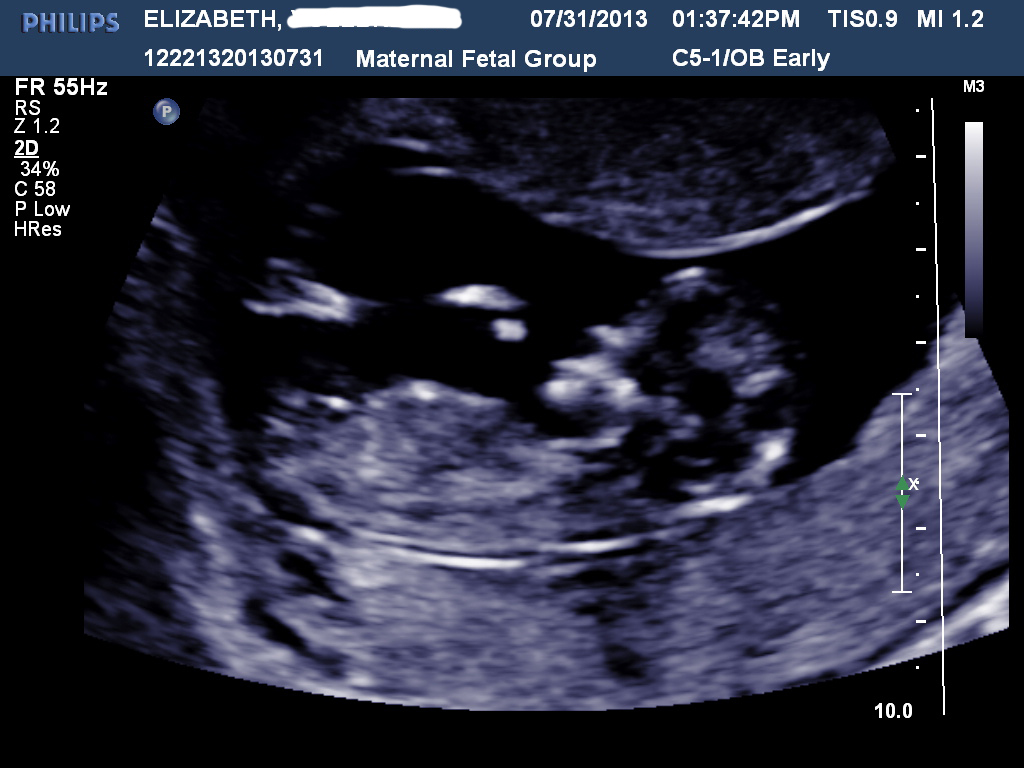

Hi all! I had my NT scan today and I'm stumped. There was no denying that my son was a boy but this baby has left me pretty stumped. I've gotten some mixed reviews elsewhere but it tends to lean one way over the other... Taken at 12w4d. So, predictions? :)

Attachment 12741